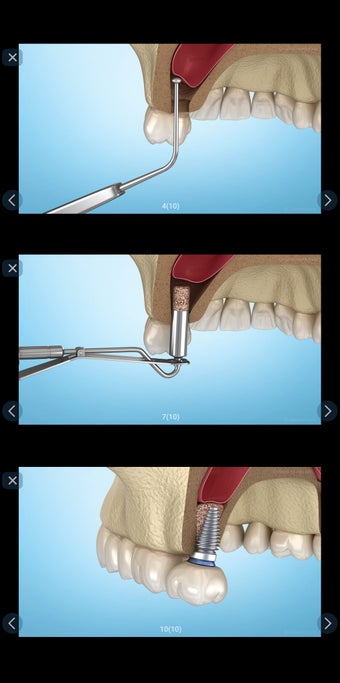

إذا كنت متخصصًا في طب الأسنان أو مريضًا، فقد تساعدك هذه الأداة في تعلم علاجات الأسنان.

تم إنشاء هذا التطبيق بواسطة أليكس ميت للأطباء الأسنان وطلاب طب الأسنان والمرضى. كما يمكن استخدامه أيضًا من قبل المهنيين الطبيين الآخرين.

يستند التطبيق على مبدأ عرض الشرائح. يحتوي كل موضوع على 3-9 صور. يمكن عرض صور أي موضوع في أي وقت.